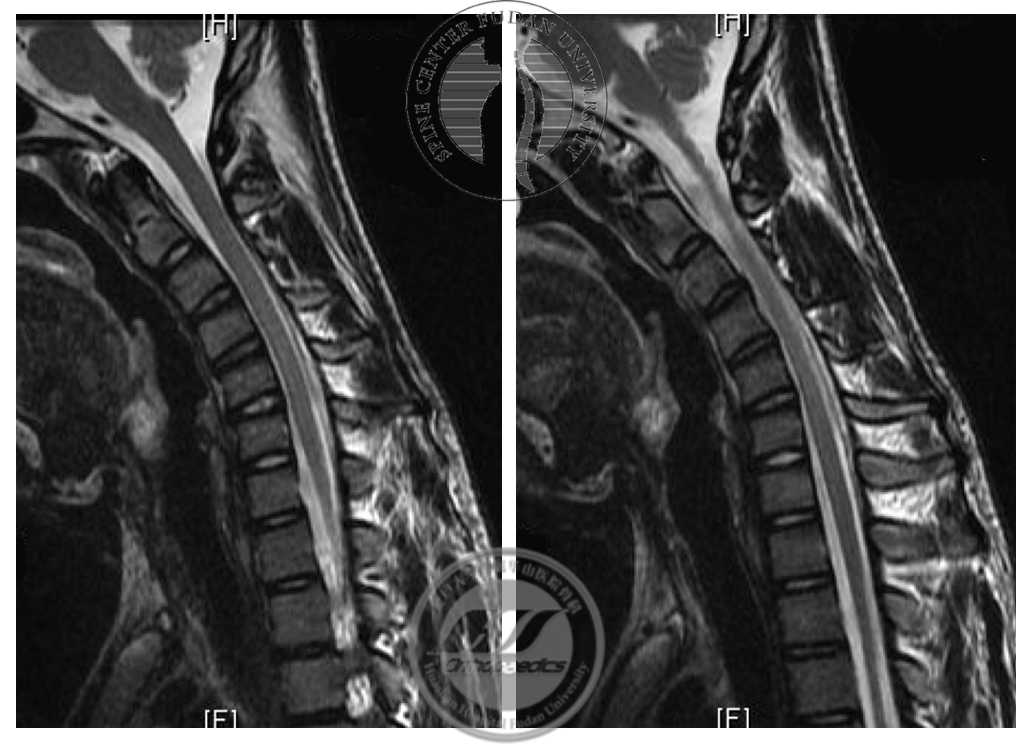

患者于2017年8月30日接受颈椎前路自体髂骨植骨融合内固定术,术后恢复良好,定期随访。最近一次随访为2019年9月(术后2年),患者诉右手握力较前增大,寒冷时症状较前好转,伸指震颤症状仍存在。X线示内固定无松动移位,屈颈位MRI显示“膜-壁分离”现象消失,屈颈位脊髓未见明显压迫,相邻节段未见明显退变(图6,7),神经电生理检查示所检肌自发电位消失,募集较前好转(图8)。

图7 术前与术后2年屈颈位MRI对比,术后T2加权像显示“膜-壁分离”现象消失